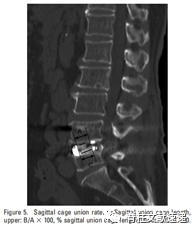

图注:矢状面Cage融合率(%)。Cage内部骨与上侧椎体终板结合处的融合率:B/AX100%;Cage内部骨与下侧椎体终板结合处的融合率:D/CX100%。

术后对其随访一年。一年后CT结果示:术后1年椎间高度平均值明显高于术前水平,椎间融合率为96.2%。Cage内部骨与上下终板结合处的融合率在冠状面为46.7%和52.2%,矢状面为46.4%和49.9%(融合率测量方法见上图)。Cage下沉高度在冠状面为1.26mm和0.72mm,矢状面为1.04mm和0.53mm。由此可以看出Cage内部骨的融合率为50%左右。因此作者建议将更多的骨组织移植到椎间隙中,而非Cage内。